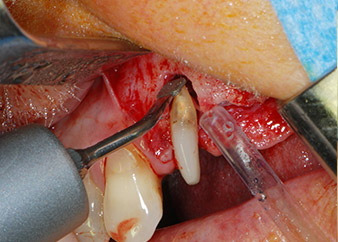

Si è mantenuta , tuttavia, l'idea iniziale di conservare entrambi i denti come appoggi temporanei del ponte durante il periodo di sei mesi per l'osteointegrazione degli impianti. In seguito la situazione si sarebbe assestata. In primo luogo, in un tentativo di risolvere il problema entro-periodontale, la superficie radicolare rimanente è stata attentamente sbrigliata con apparecchiatura piezoelettrica (Piezomed di W&H con l'attacco S1 a spatola, progettato in origine per l'erosione della parete laterale del seno mascellare) Fig. 4).

Quindi con lo stesso strumento si è passati ad abradere l'apice per rimuovere il tessuto apicale infetto residuo e per ridurre le possibili ramificazioni radicolari e canalari accessorie (apicetomia) (Fig. 5). Non è stato necessario riempimento retrogrado poiché si era appena ritrattato il riempimento ortogrado.